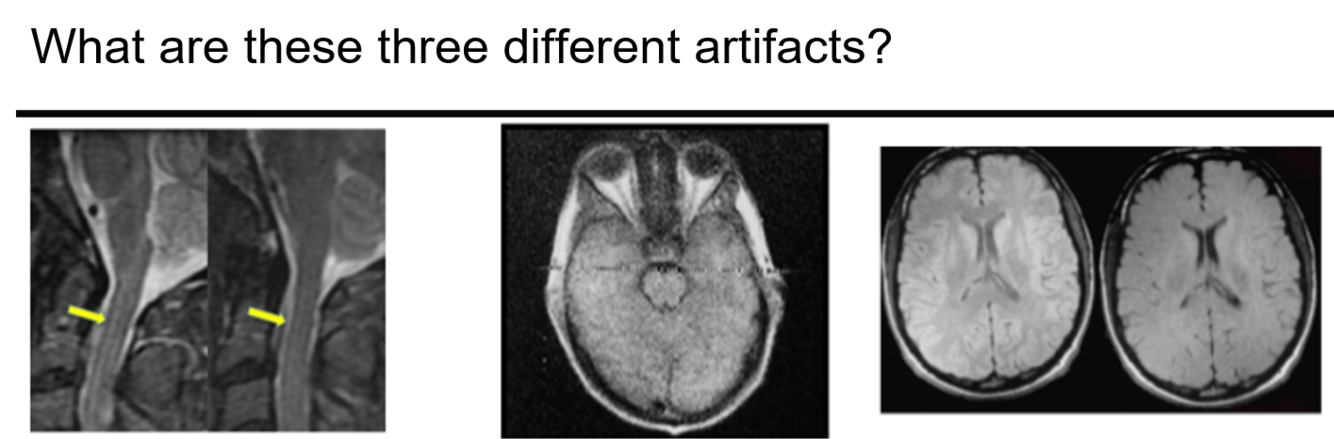

aliasing

also called Moire fringe artifact, commonly seen in GRE sequences and is a result of alternating constructive and destructive interference

Moire fringe artifact is commonly associated with what sequence?

GRE

aliasing (ear lobe into middle of image)